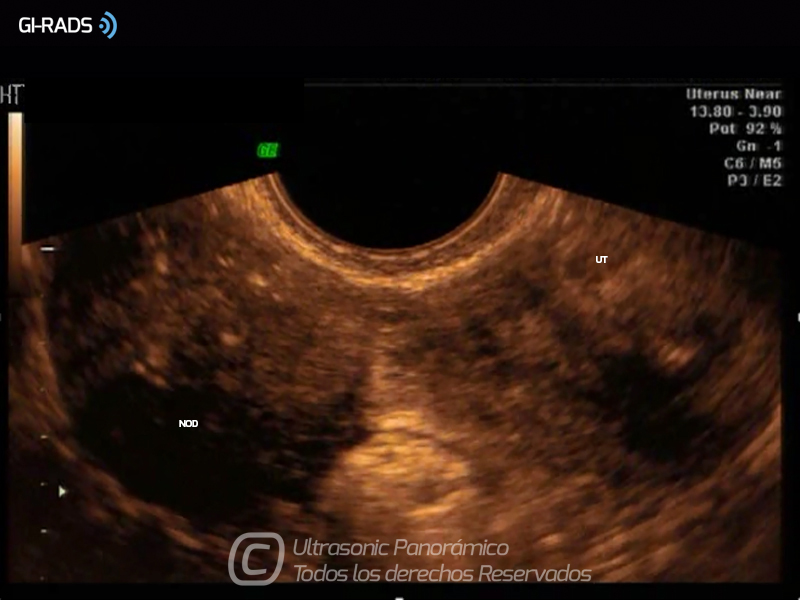

Patologías Benignas – Mioma Pediculado